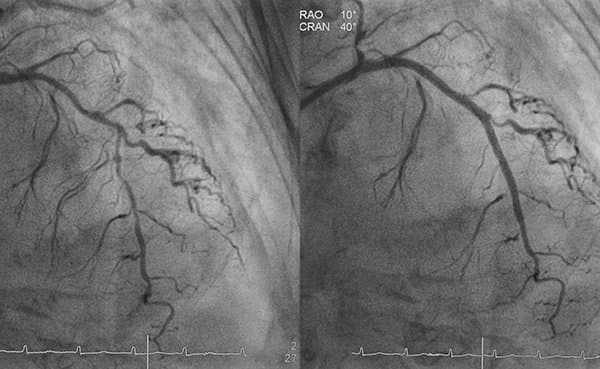

Après une angioplastie transluminale percutanée coronarienne, on se trouve confronté au dilemme du choix d’un traitement antiagrégant plaquettaire, sachant que la double inhibition plaquettaire est associée à un risque hémorragique accru – les seniors étant particulièrement à risque. Une adaptation du traitement peut être indiquée.

Différentes stratégies ont été évaluées pour réduire le risque d’hémorragies sous double inhibition de l’agrégation plaquettaire (DAPT) pour une angioplastie transluminale percutanée (ATP). L’une d’entre elles est l’arrêt précoce de l’inhibiteur du récepteur de la P2Y12 avec poursuite de l’AAS en monothérapie. Selon trois études, la désescalade précoce ne présente pas inconvénient.